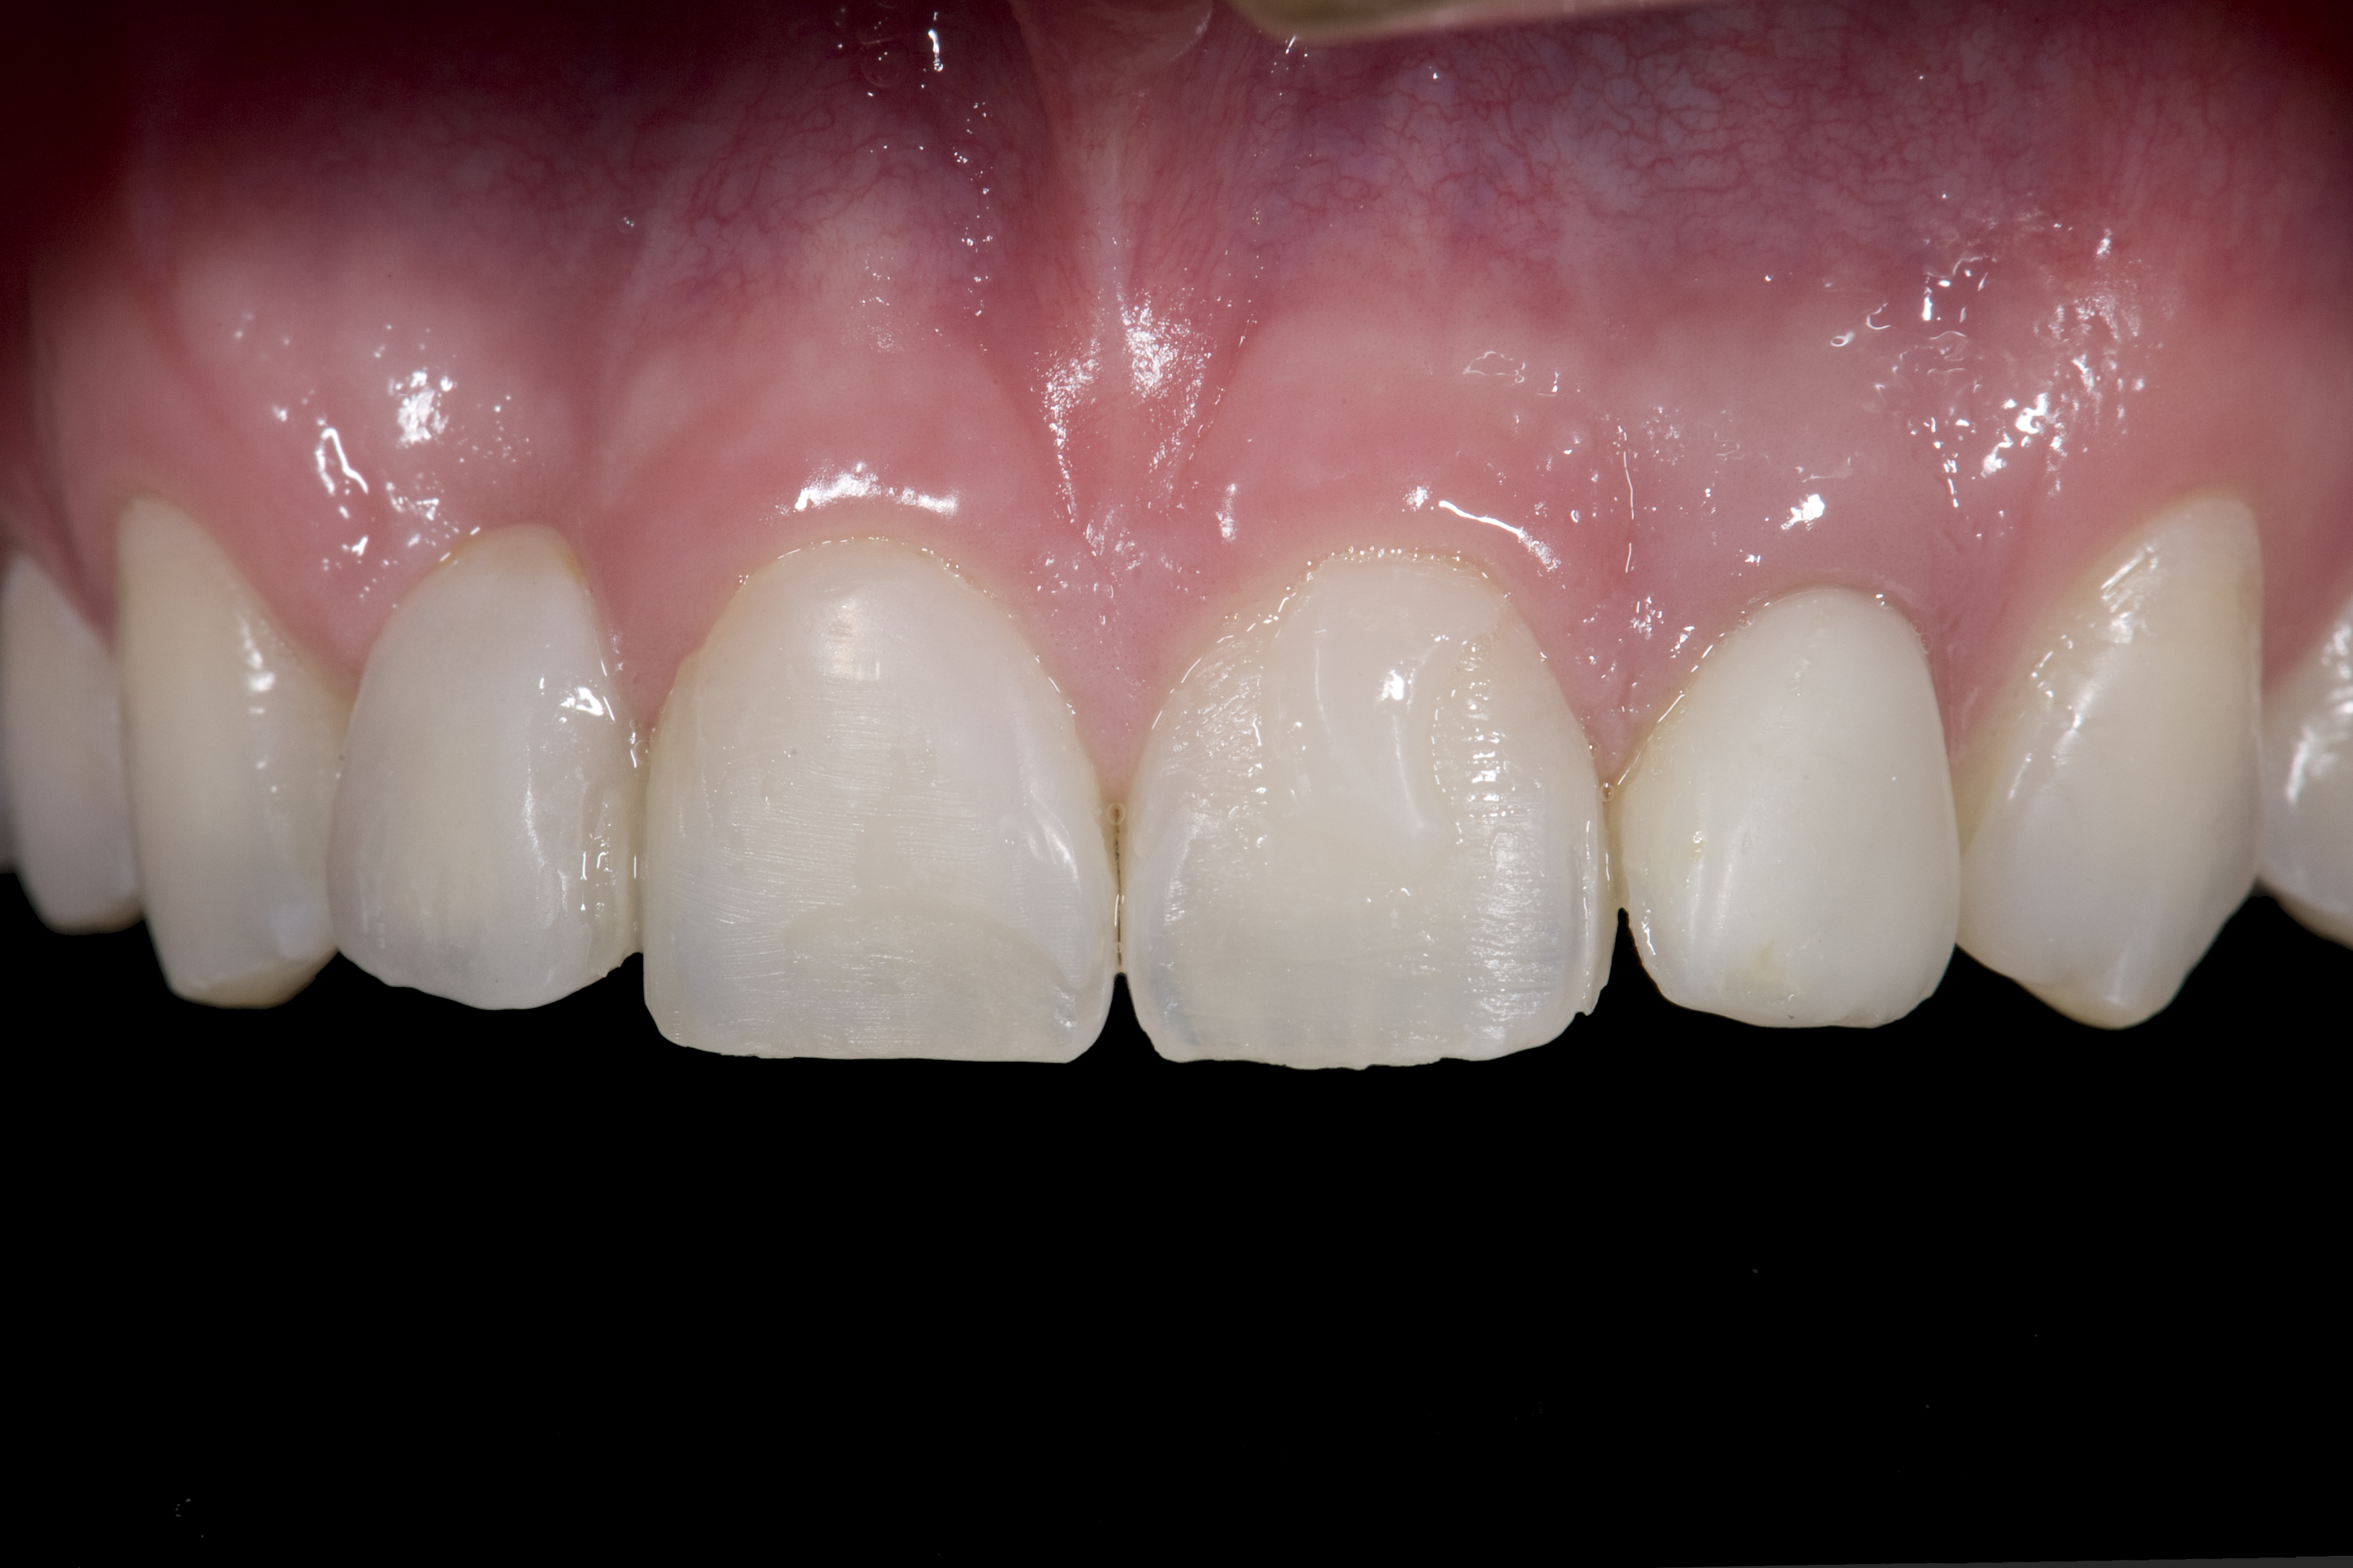

(12.) 15-year-old girl after orthodontic therapy idealized maxillary lateral incisor spaces.

Figure 12

(13.) Deficient ridges in the areas of the missing lateral incisors.

Figure 13

(14.) Occlusal view. Some form of augmentation would be needed if implants were being considered.

Figure 14